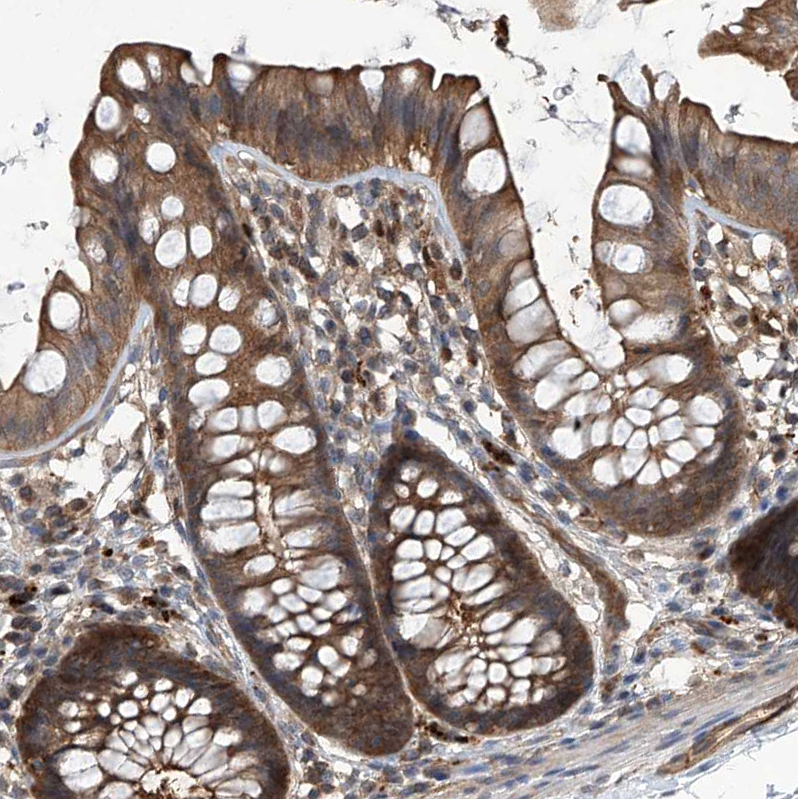

Immunohistochemical staining of human colon, kidney, liver and testis using Anti-PSMB1 antibody HPA029635 (A) shows similar protein distribution across tissues to independent antibody HPA029637 (B).